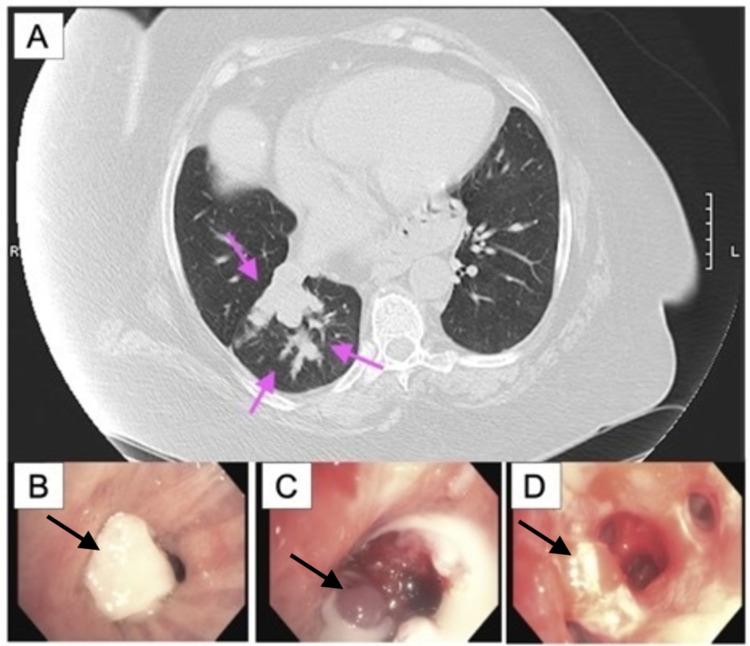

Atypical carcinoid belongs to a spectrum of neuroendocrine tumors that can present as central airway obstruction. We treated a 58-year-old female who presented with recurrent pneumonia. Flexible bronchoscopy showed complete obstruction of the tumor in the right lower lobe. The tumor was excised by electrocautery snare followed by laser and argon plasma coagulation (APC). Endobronchial biopsy showed atypical carcinoid with lymph node metastasis. Succeeding bronchoscopic management, the patient's symptoms improved. In our patient, bronchoscopy with laser and APC was performed to prevent tumor recurrence after resection and reduce the risk of recurrent postobstructive pneumonia. Surveillance computed tomography at six months showed no evidence of recurrence. Bronchoscopic management should be considered in poor surgical candidates or patients with metastatic disease.

非典型类癌属于神经内分泌肿瘤谱系,可表现为中央气道阻塞。我们治疗了一名58岁的女性,她因反复肺炎就诊。柔性支气管镜检查显示右下叶肿瘤完全阻塞。通过电圈套器切除肿瘤,随后进行激光和氩等离子体凝固(APC)治疗。支气管内活检显示为伴有淋巴结转移的非典型类癌。经过后续的支气管镜管理,患者症状有所改善。在我们的患者中,进行激光和APC支气管镜检查是为了防止切除后肿瘤复发,并降低复发性阻塞性肺炎的风险。六个月后的监测计算机断层扫描显示无复发迹象。对于手术条件差或患有转移性疾病的患者,应考虑支气管镜管理。